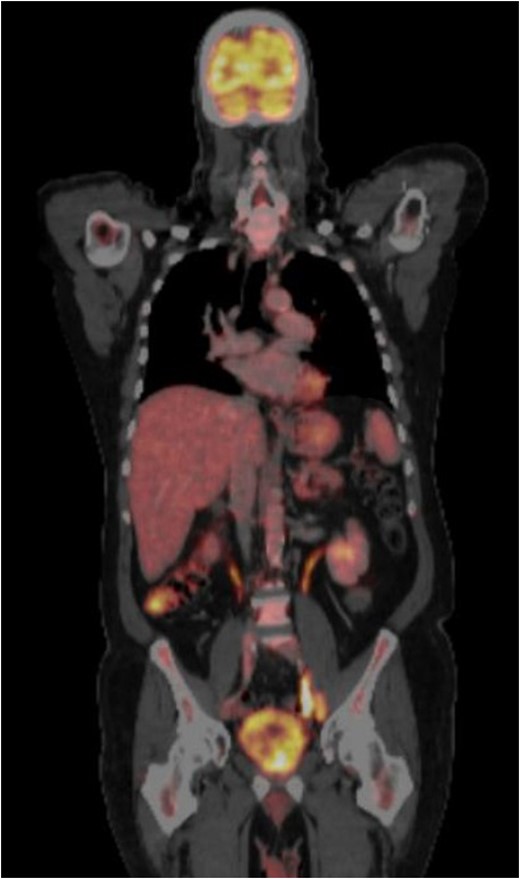

CT-PET done one year from the previous CT-PET. This showed complete remission of disease. No evidence of distant metastatic disease.